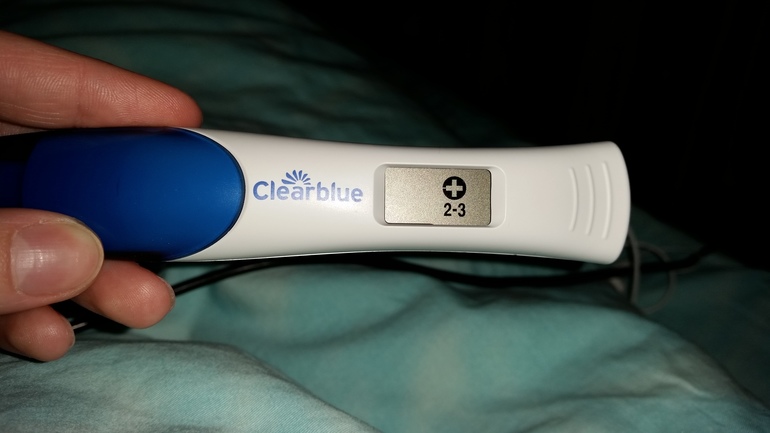

Девочки, подскажите, сделала 2 теста, один просто обычный показал 2 полоски, другой электронный он показал плюсик и 2-3 недели. Но вопрос в другом у меня очень сильно тянет живот, как перед месячными причём уже дня 4-наверное точно, пошла к врачу, не знаю какае то странная попалась, т.к пошла к первому попавшемуся, моя в отпуске и она мне даже ничего не сказала нормально это или нет, что пить может для того что бы боль прошла, т.к беременность всё таки желаемая и ожидаемая не хотелось бы что бы случилось что то. Вчера также сдала кровь ХГЧ результат 520. Помогите советом

Тест клеарблю не врет, да и хгч крови. Тянуть живот будет, может и до 2 триместра, такое у многих. Можете поинять но-шпу, если совсем невмоготу. Но не увлекаться. Чуть позже, через пару-тройку недель сделайте узи. А так, следите за выделениями. Если хотите уверенности в развитии беременности, можете посдавать хгч в динамике.

Я ходила на неделю позже такого же результата теста, как у Вас. Там все равно еле видно. Если не будет ничего беспокоить, то лучше хгч. Должен сильно расти.

у меня показало плодное яйцо на 3 день задержки, т.е. от зачатия было просто 2 недели, а от последних месячных 4 и 3 дня недели.....я не знаю, какое узи используется у вас, если через живот стандартное, то не покажет....а если через влагалищное узи, то покажет хоть в первый день, вы не увидите сам плод, но увидите черную затемненную область и желточный мешок...это и есть беременность, будет выглядеть вот так